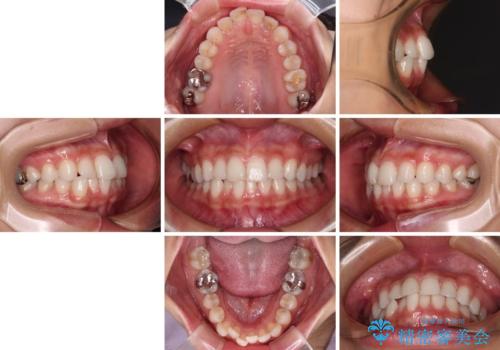

- 歯並びと虫歯をきれいにしたいとのことで来院された患者様です。

楽して短期間で歯列を整えたいとのことで、ワイヤー装置を用いて矯正治療を行い、矯正治療後に下顎の虫歯はセラミックインレー、上顎はPGAインレー(ゴールドインレー)、根管治療を行う歯についてはオールセラミッククラウンにて補綴治療を行うこととしました。

矯正治療は8ヶ月ほどで終了し、速やかに虫歯治療に移行することができました。

保険治療で用いる樹脂(コンポジットレジン)で行った虫歯治療は、周辺が変色して汚くなっていましたが、下顎はセラミックインレーで審美的に、上顎はPGAインレーで歯に負担の少ない治療を行うことができました。